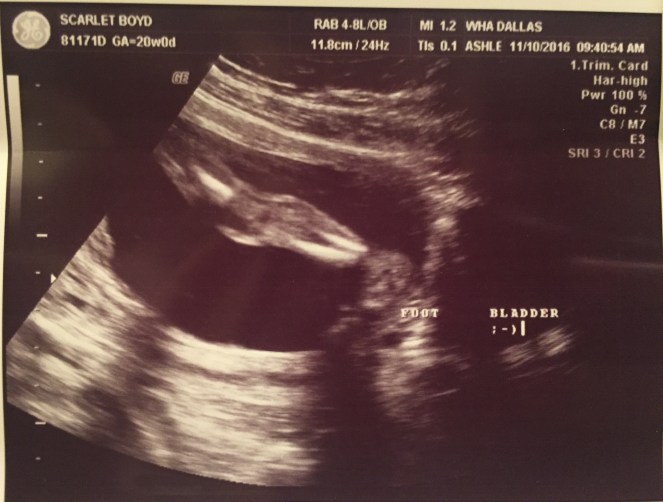

Now back to our bumpdate. We had two appointments last week: one with our OB and one with your MFM specialist. First up, our 20 week appointment with my OB. This appointment was a lot of fun! I pretty much live at the doctor’s office so I’ve become close with a lot of the staff which makes things easier…especially while sitting in a room with your belly exposed & someone running a wand over it for 30+ mins. Crockett was very active during the sono so I got to see him twist and turn all over the place . At one point it looked like he was waving at us and the sono tech said “Look! He’s got a great Miss America wave going on” and right away he elbowed her hand twice which made us giggle. Okay little man, it was a tough guy wave :). Crockett was measured for everything possible as well as checking the placenta, cord insertion, and cord blood flow. He passed every test and his growth looks great! He has doubled his weight since our last appointment to a whopping 12 ounces. He looks so big on the screen but the weight always brings me back to reality, he is so tiny right now.

They quickly got me into an exam room and the sonographer came in immediately. I don’t know if this was to sooth me or to double check he still had a heartbeat. Probably both because I’m usually waiting in that room for about 10 minutes. Once hooked up, he was doing his usual morning calisthenics. I swear, mornings are his jam. He constantly parties in the morning! This appointment we double checked all of his growth and compared it to last month. He’d grown well in all categories and they confirmed his stout 12 ounce weight. We spent a lot of time checking the placenta and his cord. It looked like he was using the placenta as a pillow…just laying his head right on top of it. He continued to wiggle the entire appointment. The sonographer called him a “wild man”, hehe! My MFM doctor came in next to continue with the sonogram and confirm everything the sonographer saw. He said Crockett is growing like a weed and couldn’t be more pleased with his progress. He also checked on my mental health. I love that he does this each appointment because he reminds me at this point to not be polite nor to sit at home scared if I think something is wrong. I told him if/when I become upset, he’d know it :).

This is a video of the sonogram at our specialist. They give us a video each time of the entire sonogram which I treasure. They are the only visual proof I had of Cora when she was still alive and I am thankful to have each one of Crockett. In this video, you can see him playing with his hands in front of his face before they take his heart rate. It’s incredible what they get up to in the womb!